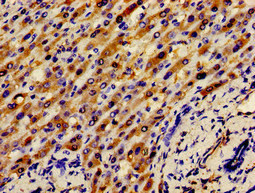

Immunohistochemistry of paraffin-embedded human liver cancer using CSB-PA11079A0Rb at dilution of 1:100